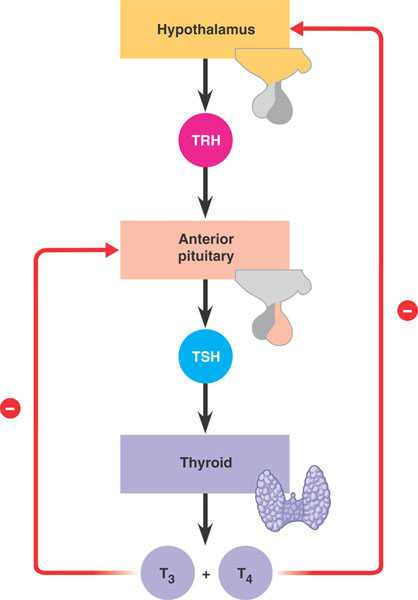

45_09T3T4FeedbackRegulat_L

thyroid.html